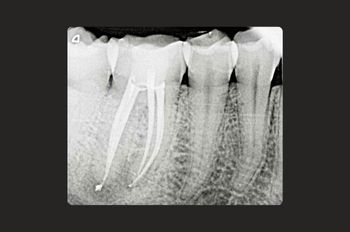

Our dentists here at Moltons Dental use the most up-to-date equipment to:

• Diagnose: We offer accurate and timely diagnoses.

• Act: Our gentle-handed dentists can remove the infection from the tooth using minimally invasive dental tools, a dental microscope, and state-of-the-art equipment.

• Prevent: We create protective and aesthetically pleasing crowns to restore the tooth’s appearance and functionality, thereby reducing the likelihood of further infections.

Our dentists are highly skilled in using cutting-edge technology to deliver long-lasting treatments that will secure your oral health for years to come.